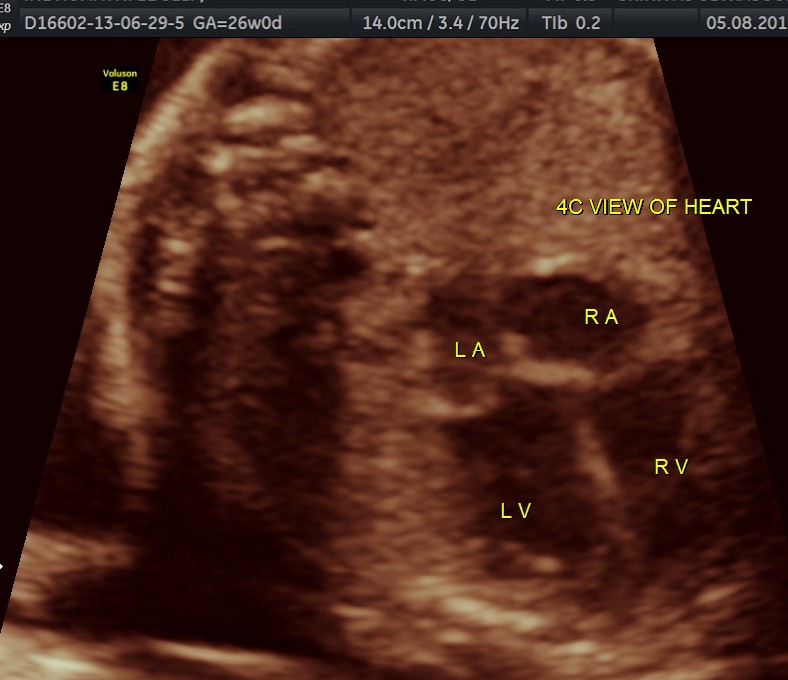

The following are of the 26 weeks gestation.

The 4 chamber view shows the patent foramen ovale. 2 pulmonary veins are also seen entering the left atrium.